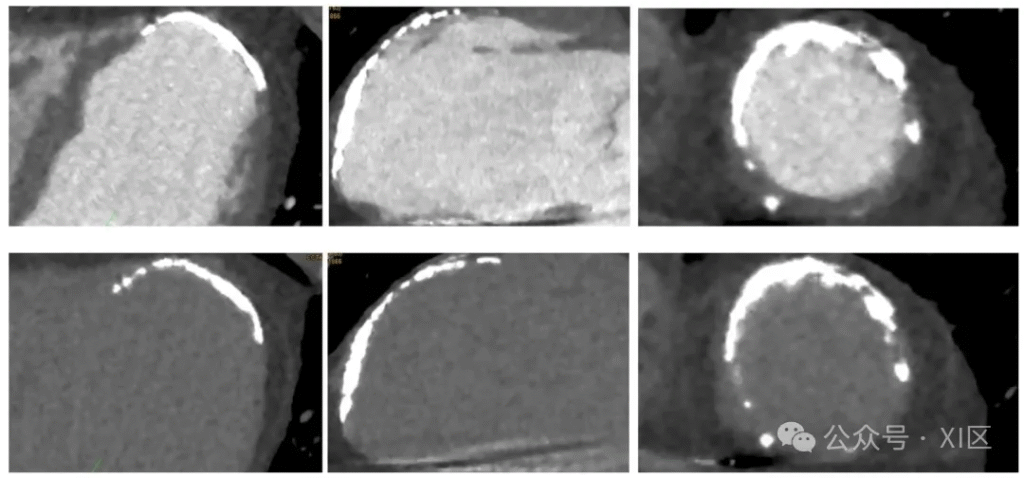

心脏计算机断层扫描(CCT)在室性心动过速(VT)消融中的应用。一名 55 岁缺血性心肌病患者,有广泛心肌梗死病史,为排除左心室(LV)血栓接受 CCT 检查。上图展示左心室的三腔心、两腔心及短轴位增强 CCT 图像;下图为延迟期成像,左心室心尖部、前壁及前间隔部心肌存在严重钙化且运动消失,但造影剂呈均匀强化,可安全排除血栓。该增强 CCT 图像在围手术期用于指导消融操作 。